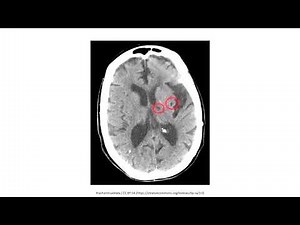

Cerebrovascular disease Symptoms